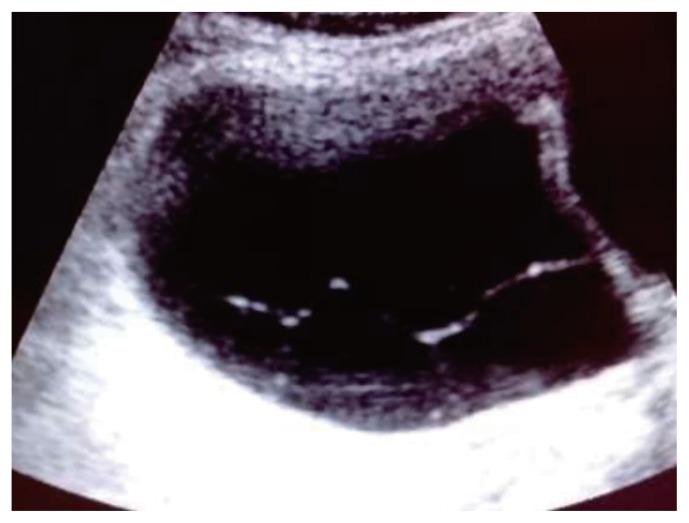

This observational longitudinal prospective analysis of 60 patients was performed over a period of 2 years (2017- 2019). The mean age of the patients was 43.75 years. Ultrasonography of ovarian masses were evaluated, and cancer antigen-125 (CA-125) levels were evaluated. Based on the IOTA classification, the B and M features of adnexal masses were studied. Color Doppler imaging was performed to evaluate the patterns of vascularity and indices.

Sixty patients with 35 benign, 23 malignant, and two borderline lesions were included in the study. In malignant lesions, 17 women (73.9%) were above the age of 45. The CA-125 cut off was ≥35 internatioal units/mL. Based on the IOTA classification, 27/35 (77.1%) benign cases, were correctly identified as benign, 6/35 (17.1%) benign cases were incorrectly identified as malignant, and two (5.7%) were found to be inconclusive. In the malignant group, 17 of the 23 patients were identified as having malignancy. Color Doppler showed three (18.8%) benign tumors had a pulsatality index (PI) of <0.8 and 21 malignant tumors had a PI of <0.8. Four benign tumors had an resistive index (RI) of <0.6 and 100% of malignant tumors had an RI <0.6.

方法

本研究纳入了60例患者,其中35例为良性病变,23例为恶性病变,2例为交界性病变。在恶性病变中,17名女性(73.9%)年龄超过45岁。CA - 125临界值为≥35国际单位/毫升。基于IOTA分类,35例良性病例中有27例(77.1%)被正确鉴定为良性,35例良性病例中有6例(17.1%)被错误鉴定为恶性,2例(5.7%)结果不明确。在恶性组中,23例患者中有17例被鉴定为患有恶性肿瘤。彩色多普勒显示3例(18.8%)良性肿瘤的搏动指数(PI)<0.8,21例恶性肿瘤的PI<0.8。4例良性肿瘤的阻力指数(RI)<0.6,100%的恶性肿瘤RI<0.6。